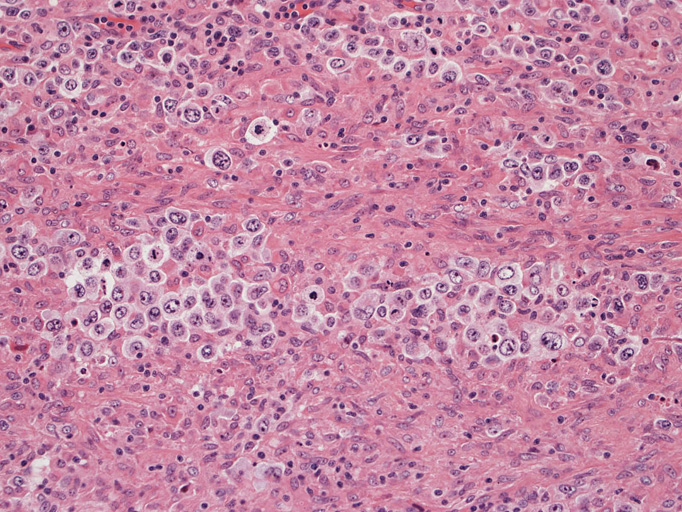

大型腫瘍細胞のシート状増殖はみられない。多彩な反応性背景をもちRS細胞様巨細胞が散在性に出現しホジキン病や反応性病変との鑑別が問題となる。

結節構造内では, 好酸性細胞質をもつ組織球の増生を背景に大型異型細胞が散在性または集蔟して増殖している。被膜下にも線維化組織内にbizzarreな大型細胞が認められる。リンパ球は小型リンパ球が大型異型細胞を含む組織球性の結節辺縁に存在する。大型細胞は, centroblastic cellが多く, その他 Hodgkin cell-like cell, RS細胞様巨細胞, 腎臓型の核をもった細胞, 多型核の細胞など多彩な形態を示す。異型核分裂像をふくむ核分裂像が多い。

大型異型細胞の形態